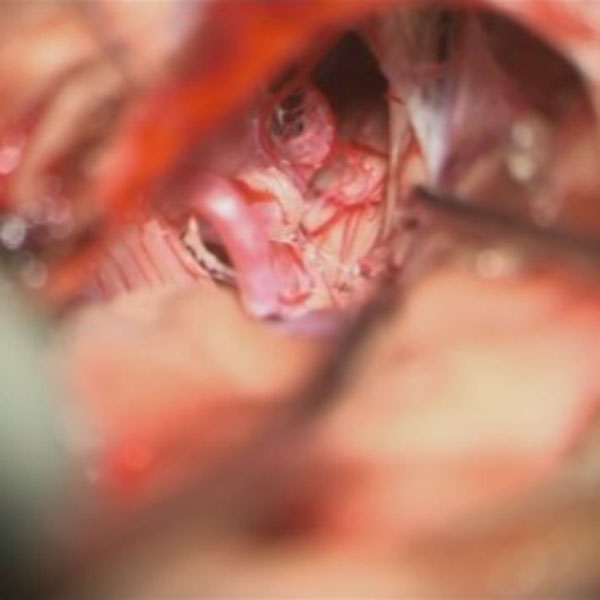

手術中

処置前